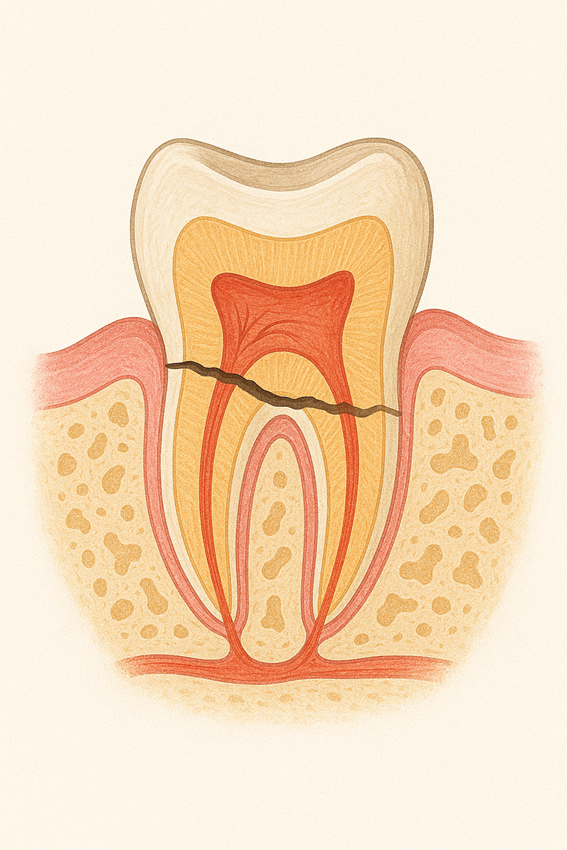

歯の根が割れてしまう状態を「歯根破折」といいます。

多くの歯科医院では、この診断が下されると抜歯が一般的な選択になります。

しかし、割れた位置や残っている歯の量によっては、抜歯せずに治せる場合があります。

当院ではまず、マイクロスコープやCTなどの精密機器で歯根の状態を詳細に検査します。もし歯の根が1/3程度以上残っていることが確認できれば、下記の処置で歯を残せることがあります。

適応できるケースは限られますが、「抜くしかない」と言われた歯が残せる可能性はあります。諦める前に、ぜひ一度ご相談ください。